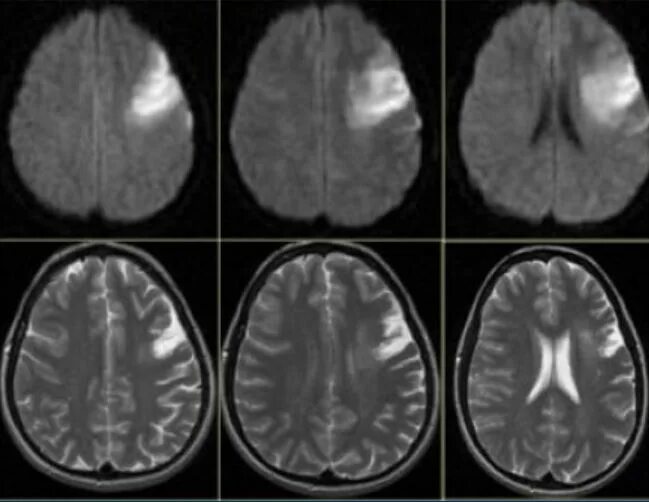

Очаги хронической ишемии головного мозга